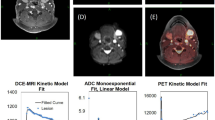

Imaging

Figure 2 illustrates the multiparametric imaging with the three different imaging modalities from a patient, FDG uptake (Fig. 2a), diffusion (Fig. 2b) and perfusion (Fig. 2c). The DWI with the RESOLVE sequence did in some cases show image distortion and signal drop out. As a consequence, only the results from the ‘standard’ DWI acquisition were used in the spatial correlation analysis. Unsurprisingly, considering the small size of the TMA cores, there was essentially no variation in imaging metrics across the cores (Supplementary Material Fig. S3). Hence, SUVmean and ADCmean were used in the correlation analyses. For DCE perfusion, the most frequent measure reported in the literature is the transfer coefficient Ktrans15, and this was used in the subsequent correlation analyses.

a An image from the 3D-morphometric scan of the specimen. b The 3D-morphometric scan fused with the digitalised pathology. c The FDG-PET scan. d The DWI scan. e The DCE scan. The black contour illustrates the tumour defined by the pathologist, and the black circle represents the areas where the core biopsy was taken. f illustrates an example from the TMA block stained with p53. The black circle depicts the core biopsy shown above (a–e). In panel g, the core biopsy is magnified. h shows the same TMA stained for CAIX, and in panel i the core biopsy is magnified.

Table 2 shows the results from the partial correlation analysis with 95% confidence intervals. FDG uptake correlated positively with both percentage of VTC and tumour cell count in the biopsy cores, and there was a significantly positive correlation between the hypoxic marker CAIX and FDG uptake. There was a significant and positive correlation between DWI and the apoptotic IHC marker p53 and DWI correlated significantly and negatively with the proliferation IHC marker Ki-67, the apoptotic IHC biomarker Bcl-2 and with the immune checkpoint inhibitor PD-L1. Moreover, Ktrans correlated positively with p53. However, despite being significant, all correlations were weak at best. After correction for multiple comparisons with the Bonferroni correction, the correlation between FDG uptake and VTC was significant as were the correlations between diffusion (ADC) and Ki-67, PD-L1 and Bcl-2.